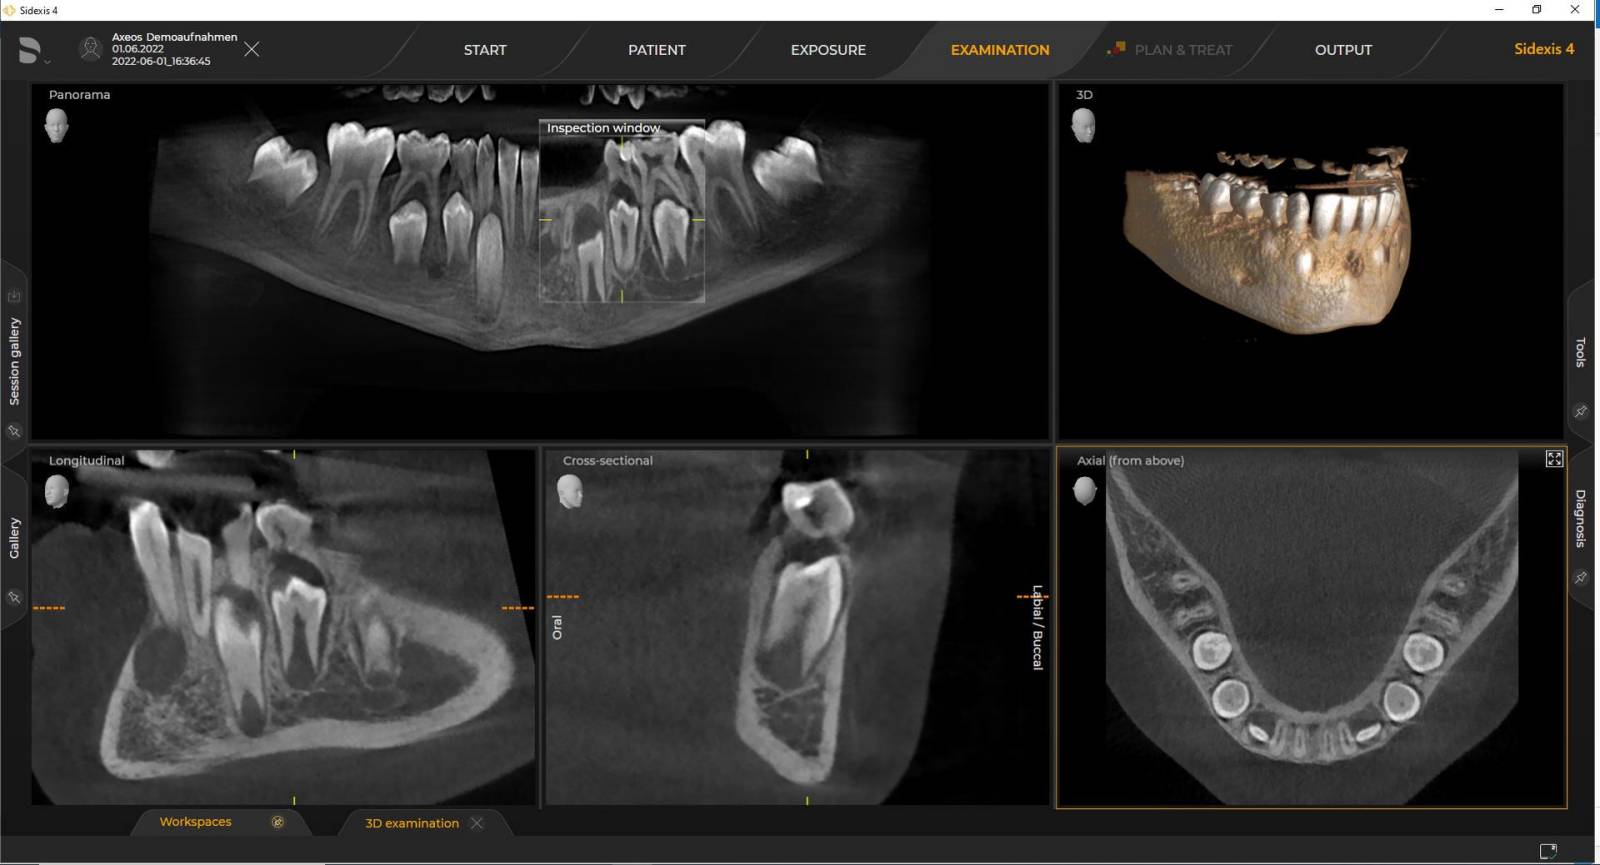

Numerous volume sizes ensure flexibility in everyday practice. Examine a precise area or evaluate the complete dentition including the TMJs

The Direct Conversion Sensor (DCS) has revolutionised the standard of panoramic imaging. X-rays are converted directly into electrical signals. Thus, there is no signal loss due to light conversion, as is the case with conventional systems. The result: images with a high level of sharpness and contrast – even at an extremely low radiation dose. For accurate diagnostic information to support targeted treatment.

The right focus is crucial for excellent panoramic radiographs. With the autofocus function you will automatically receive an image with the best possible sharpness in focus. Dentsply Sirona Imaging devices take several thousand individual images in one cycle and automatically identify the areas where the jaw is optimally positioned. Without any additional manual steps, these images are then displayed in a final sharp image.

The system detects the relevant areas from several thousand individual images in one cycle and automatically identifies the areas where the jaw is optimally positioned.

Sharp images.

Dentsply Sirona 3D units work exclusively with Sidexis 4. Nevertheless data migration from Sidexis XG to Sidexis 4 is very easy. Sidexis 4 allows for the full digital experience with the latest tools.